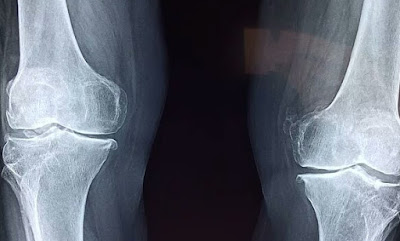

Sakit punggung dapat disebabkan oleh slipped disk, sciatica, sacro-illac, dan lainnya.

Slipped Disk dimulai dari kanal tulang belakang, urat syaraf, agar-agar inti, dan akhirnya pada Disk tersebut. Ketika akar urat syaraf tertekan, Disk akan tergelincir, menyebabkan Inti Pulposa Hernia (Herniated Nucleus Pulposa). Sciatica adalah serupa dengan Slipped Disk, hanya saja rasa nyerinya sangat tajam dan seperti tersengat listrik, turun menuju kanal tulang belakang, mengirimkan rasa sakit yang hebat dimulai dari bagian belakang dan berjalan menuju kaki. Rasa nyerinya berselang berulang-ulang, dimana suatu saat akan mengakibatkan sindrom rasa sakit yang Glossary Link kronis.